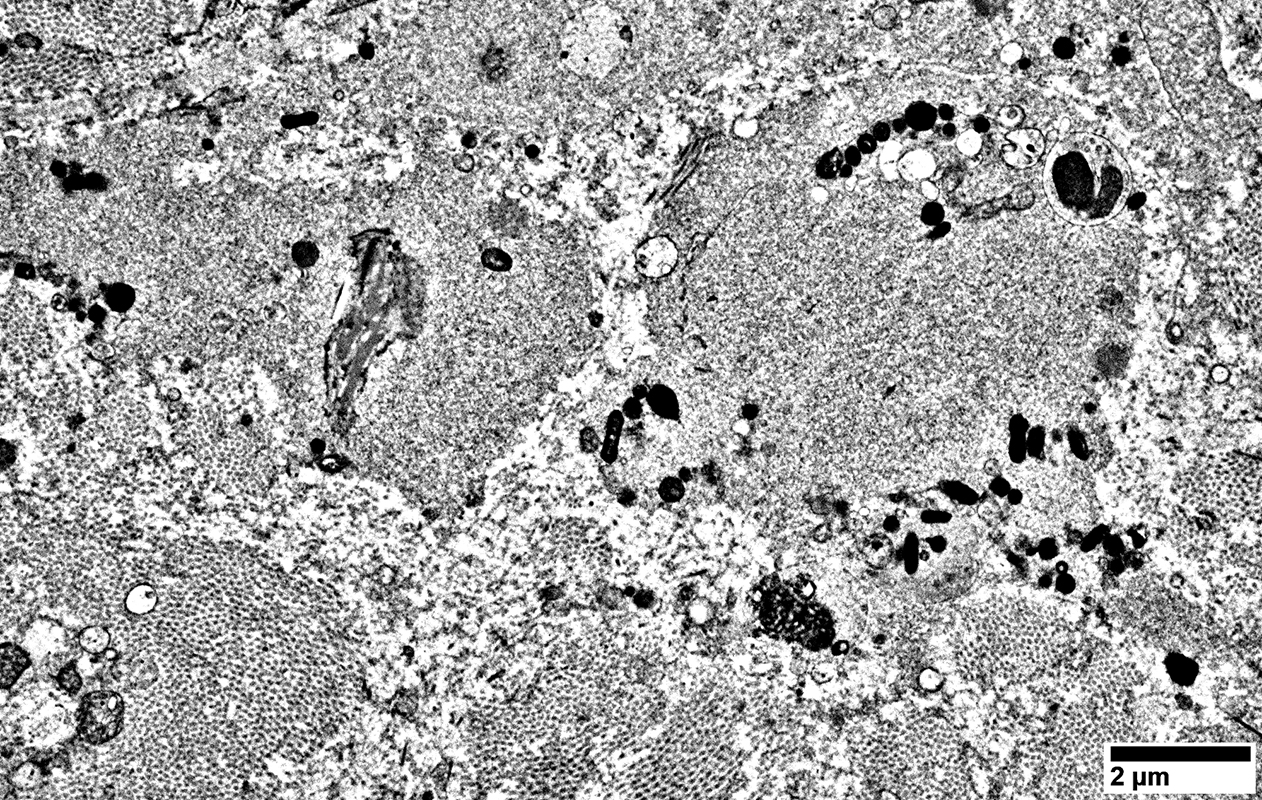

Regenerating Axons

Clusters of processes

2 types of contents

Tubulovesicular profiles

Densely distributed in axon processes

Compare to:

Axons, large & proximal to nerve lesion

Organelles, including many mitochondria

No surrounding Schwann cell cytoplasm

From: R Schmidt

Cluster of moderate-sized processes

All contain mainly Tubulovesicular profiles

Densely distributed

Cluster of processes

Tubulovesicular profiles surrounded by Organelles, including many mitochondria

Mixed contents: Tubulovesicular profiles & Organelles